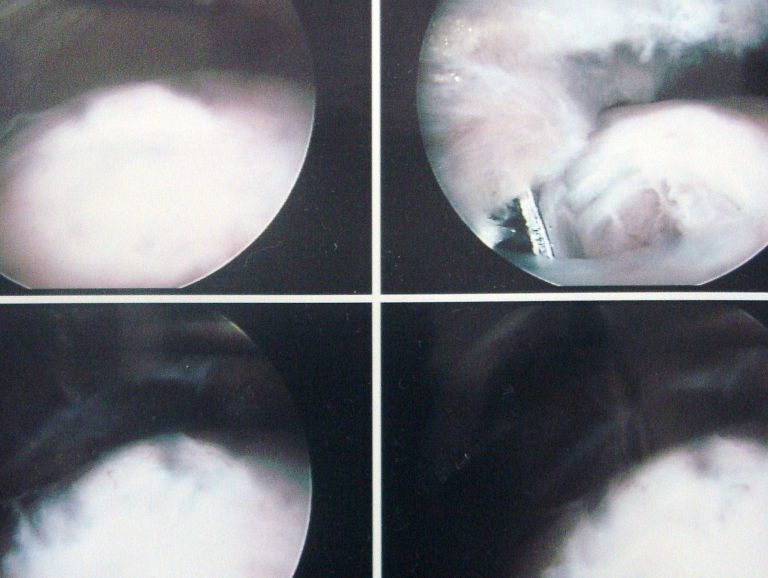

홈치료증례관절내시경수술어깨관절 어깨관절 전체 4 최신순 추천순 조회순 업데이트순 관절와순파열 관절 내시경 수술 관리자 | 2010.07.17 | 2263 견봉쇄골 관절 탈구 및 회전근개파열 수술 관리자 | 2009.01.21 | 2138 회전근개파열 관절내시경 수술 관리자 | 2008.11.06 | 2047 회전근개파열수술 관리자 | 2008.10.22 | 1989 1 전체 제목 내용 작성자 검색